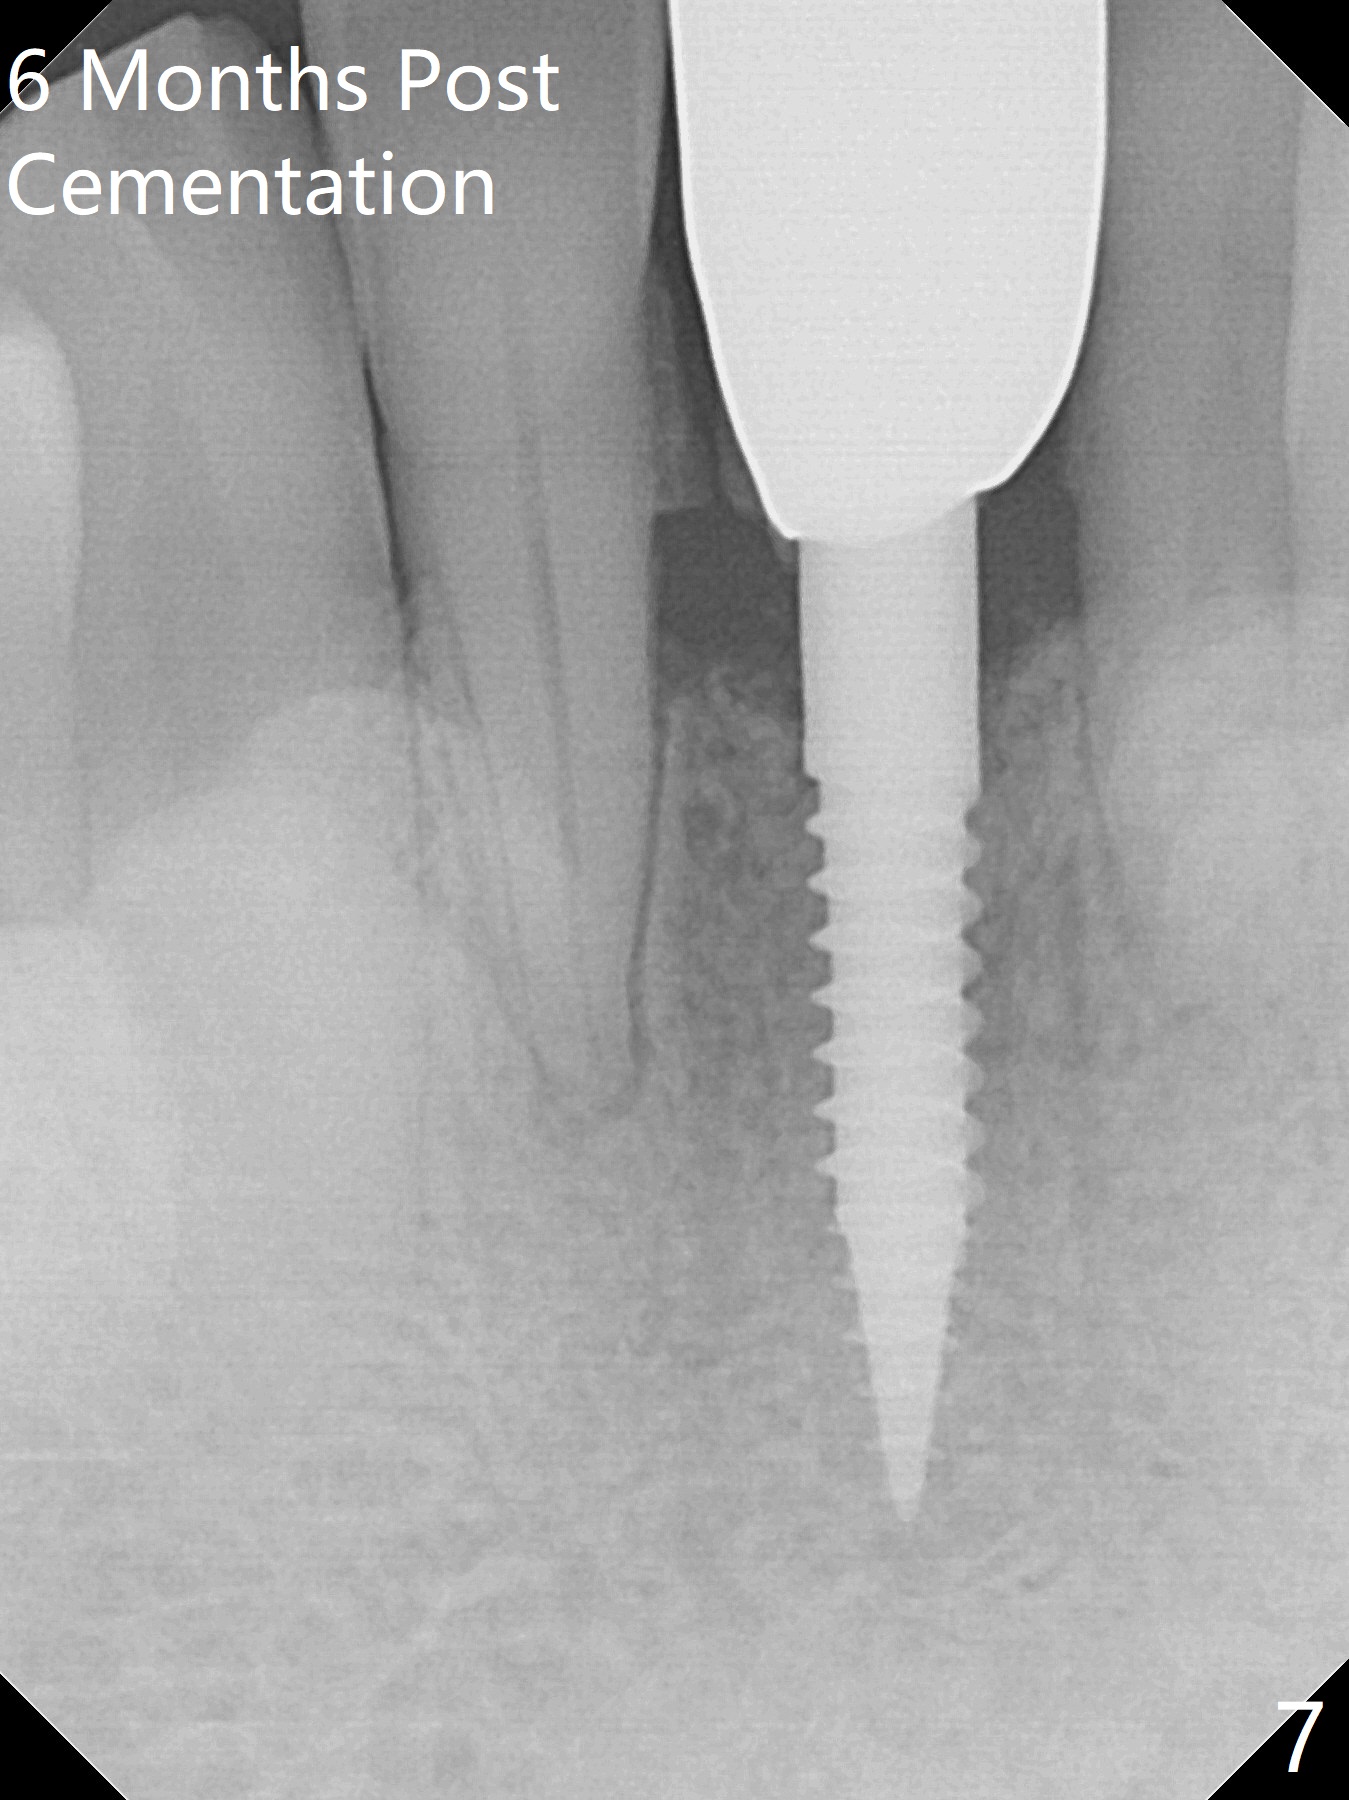

When the patient returns for implant placement 1.5 years after the last treatment (SRP), the tooth #25 has exfoliated, whereas the tooth #24 is severely displaced (Fig.1-3).  In fact the buccolingual plates are found to be lost after extraction, corresponding to change in gingival color indicated by an arrowhead in Fig.1.  Initial osteotomy with 1.2 mm drill is parallel to the terminal branches of the Incisive Canal (Fig.4 arrowheads).  Since the gingiva is as thick as 7.5 mm (Fig.3 arrow), a 3x14 mm 1-piece implant with 4 mm cuff is placed (Fig.5); three implant threads are outside the native bone; with allograft (*) placed and the neighboring crests being coronal to the threads, the chance of periimplantitis should be remote.  An immediate provisional is fabricated to contain the graft in place.  Meanwhile the tooth #2 is symptomatic with crack.  The top 3 threads appear to be contacted by the newly formed crestal bone 6 months postop (Fig.6 *).  Bone appears to have grown into the space between implant threads 6 months post cementation (13 months postop).